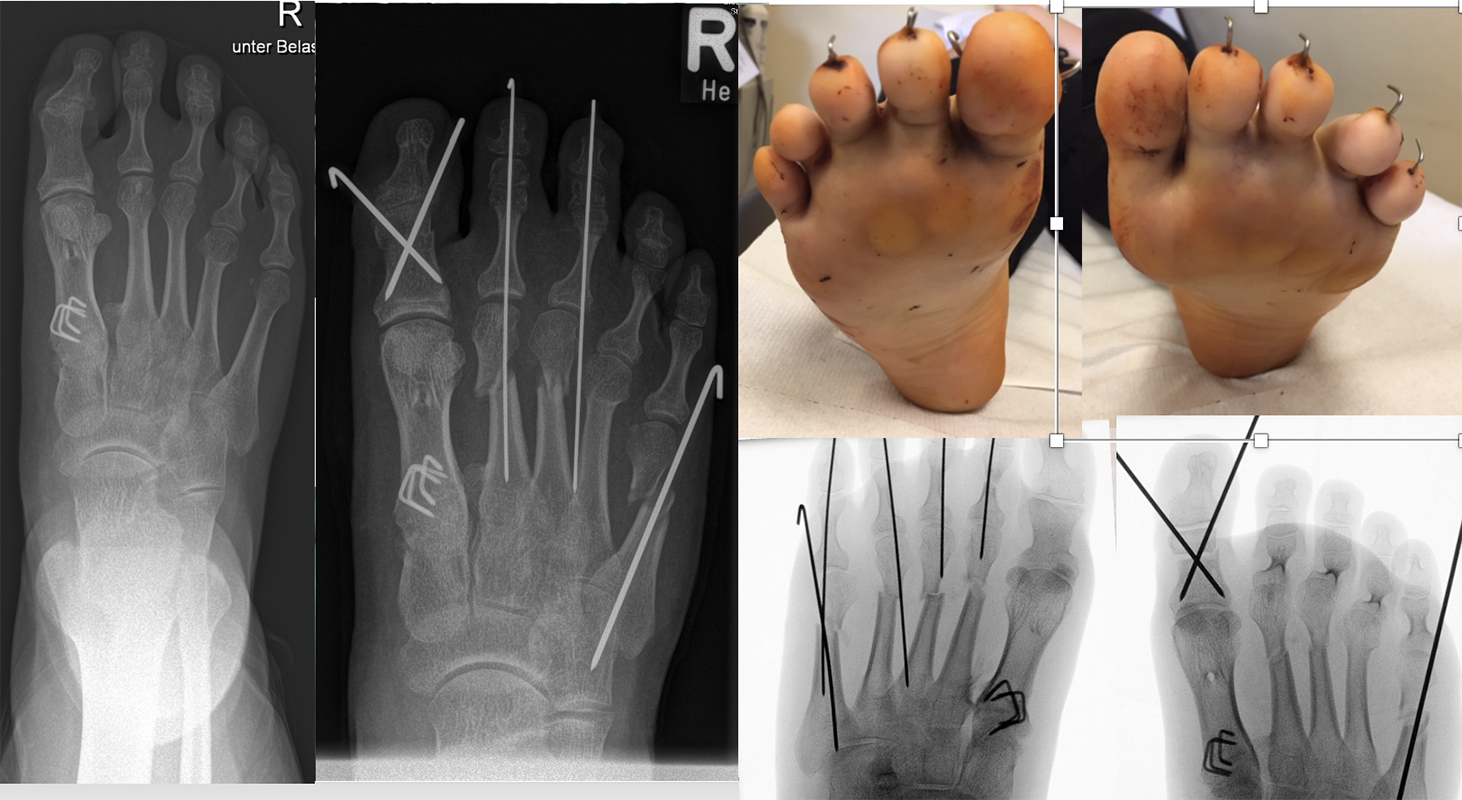

Hohlfußkorrektur nach Gebhard Suger (Frank Mattes/Anja Helmers)

In einem kinderorthopädischen Beitrag im Augsburger MIS Kurs im September 2021 erfolgte von unserer Seite die Vorstellung der Therapie der hyperpronierten Metatarsalia II-IV beim Ballen-Hohlfuß/HMSN (Hereditäre motorisch-sensible Neuropathie) mit der minimalinvasiven DMDO an zwei Patienten an je zwei Füßen (Abb. 29).

Abb. 29: Jugendliche Patientin mit familiärer HMSN (Hereditäre motorisch-sensibel Neuropathie) und Schmerzen unter den Metatarsaleköpfchen II-IV bei erhöhter Vorfußlast. DMDO zur Druckentlastung und MT V zur Reduktion der Vorfußbreite.

Im praktischen Teil des Kurses wurde von Gebhard Suger ein anderes Konzept zur minimalinvasiven Behandlung des milden bis mittelschweren Ballen-Hohlfußes angeregt, welches er in seiner aktiven Zeit mit Erfolg durchgeführt hat (Abb. 30).

Unter der Anleitung von Gebhard Suger wurde folgende OP-Abfolge entwickelt. Bis zum jetzigen Zeitpunkt konnten insgesamt sechs Füße an sechs unterschiedlichen Patienten wie folgt versorgt werden.

=> Krallenzehen

Entsprechende Krallenzehenfehlstellungen können additiv minimalinvasiv korrigiert werden. Da es sich um eine funktionelle Fehlstellung handelt (Extensorensubstitution bei fehlender Fußhebung) kann bei Kindern, Jugendlichen und Jung-Erwachsenen die weitere Entwicklung nach Verstärkung der Fußhebung durch den M. tibialis posterior Sehnentransfer abgewartet werden. Nicht selten reduzieren sich die Krallenzehenfehlstellungen durch die postoperativ verbesserte Fußhebung. Ansonsten erfolgt die minimalinvasive Krallenzehenkorrektur in üblicher Weise.

Abb. 39 a-b: Minimalinvasive Krallenzehenkorrektur mit präoperativen und intraoperativen Röntgenaufnahmen (a) und klinischem Bild prä- und postoperativ (b).

Beim Ballen-Hohlfuß wird aufgrund der Rezidivneigung häufig ein Girdlestone-Taylor Beugesehnentransfer kombiniert angewendet.

Abb. 40 a-f: Kompletter klinischer und radiologischer Verlauf eines schweren Ballenhohlfußes: Bild im Stand mehrere Ansichten sowie radiologische Diagnostik präoperativ (a), percutane Ablösung der Plantarfaszie als ersten operativen Schritt (b), radiologisch sichtbare Osteot0mien MT I-V sowie klinisches Ergebnis intraoperativ (c-d), klinische Gegenüberstellungen der präoperativen Fehlstellung und der postoperativen Korrektur (e); zweites Beispiel eine spastische Hohlfußfehlstellung im prä- und postoperativen klinischen Verlauf (f).